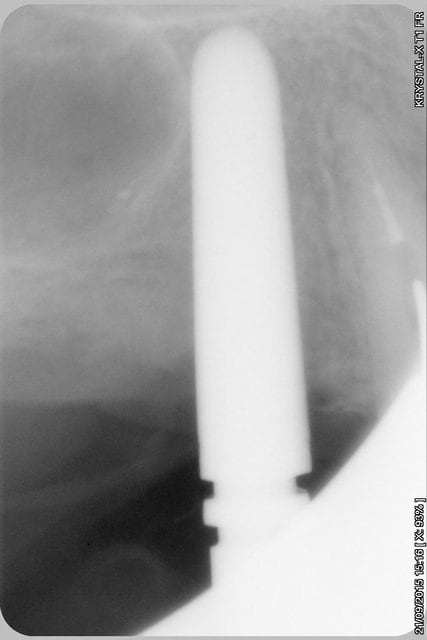

La rx avec bistouri en place sert à vérifier quoi?

la radio sert à vérifier la position de la lame 15, par rapport à la racine et au sinus, mais je ne suis pas sur que tu comprennes, que le bistouri est dans l'os, c'est l'instrument le plus fin et le moins traumatisant pour fendre l'os (je le préfère au piezzo et même au disque diamanté).